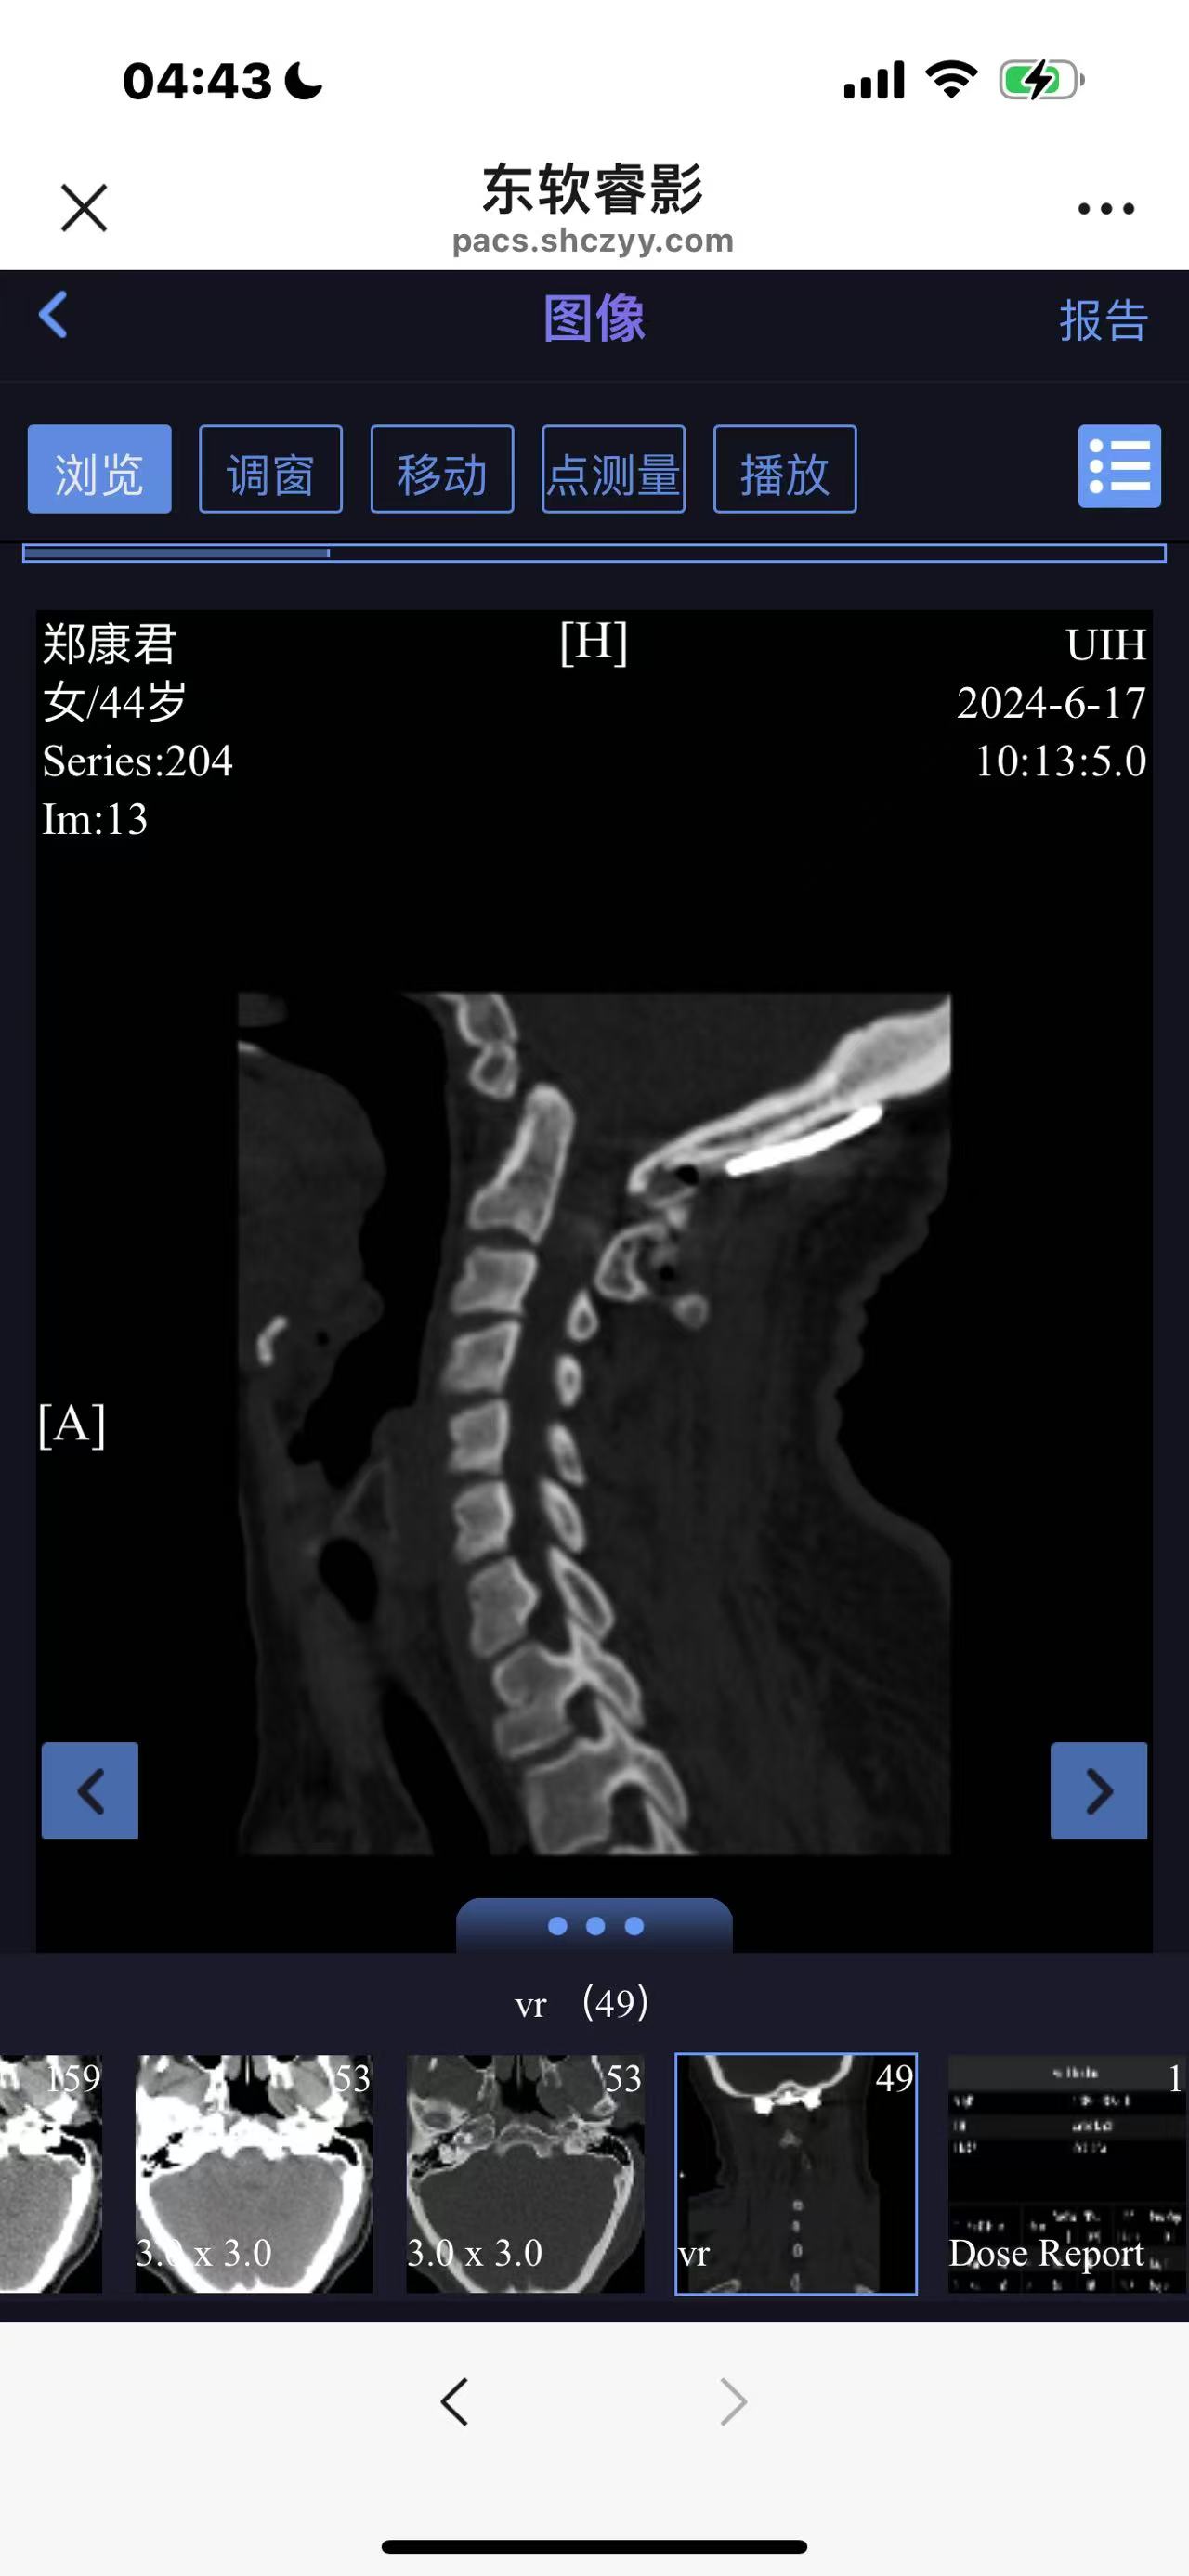

• 诊断:寰枢椎脱位

• 影像:

• 日期:2024.06